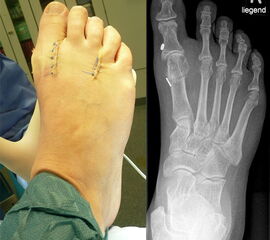

Klinisches Erscheinungsbild eines Hallux varus (eigenes Bildmaterial)

Abbildung 1